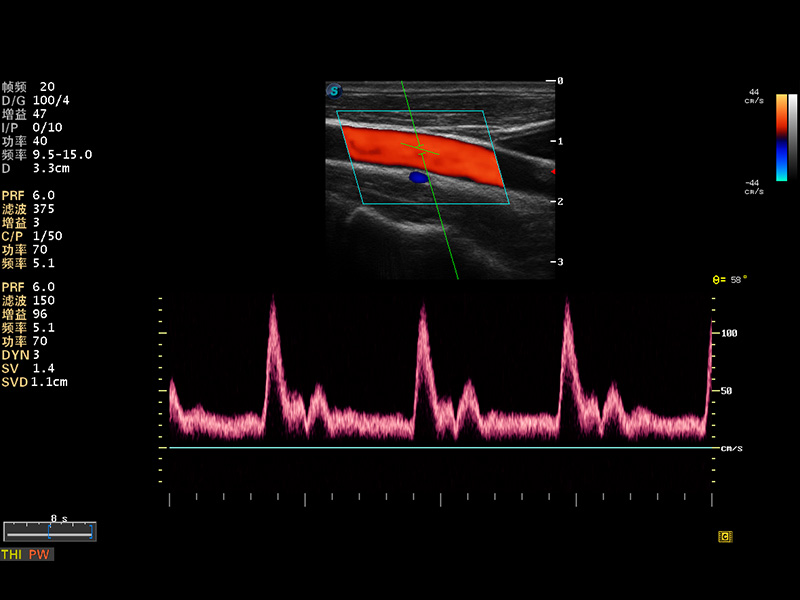

S8 EXP便携式彩色多普勒超声诊断仪是百老汇电子游戏官网研发的高端全身应用型便携彩超。高通道的VIS平台融合可视化(Visual)、智能化(Intelligent)和人性化(Smart)的特点,配以百老汇电子游戏官网自主研发生产的探头大家族,使您能够快速、准确的获得病人信息,提高工作效率的同时减轻疲劳。

成像技术

多波束形成器

μ-Scan微米成像

谐波成像

实时宽景成像

空间复合成像

3D/4D成像